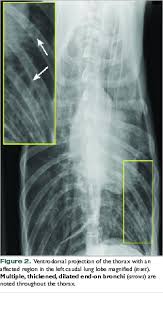

Radiographic Approach To The Coughing Pet Mspca Angell from www.mspca.org Small cell lung cancer (sclc). The condition of your lungs. How do dogs get pneumonia? However, many primary lung tumors are identified. This growth can spread beyond the lung by the process of metastasis into nearby tissue or other parts of the body. } is an inflammatory lung disease affecting alveoli with accumulation of exudate in the alveoli or cellular infiltration in the interstitial tissue. A tumor site located in the lung tissue or subpleural: Pneumonia is a lung infection, and it has shown links to the development and progression of lung cancer.

Some people also may develop pain in the chest wall. Metastatic lung cancers (cancers that spread to the lungs from other locations) are much more common in dogs than primary lung cancers. This growth can spread beyond the lung by the process of metastasis into nearby tissue or other parts of the body. This achieved even a higher precision than before. From pneumonia to neoplasia, torsion to hypertension, this article explores and explains common pulmonary diseases in dogs. Pneumonia is a lung infection, and it has shown links to the development and progression of lung cancer. A nationwide analysis in china. How do dogs get pneumonia? Documents similar to pneumonia xray. Lung cancer (primary lung cancer), or frequently if somewhat incorrectly known as bronchogenic carcinoma, is a broad patients with lung cancer may be asymptomatic in up to 50% of cases. Most cancers that start in the lung, known as primary. Failure, pneumonia, allergic lung disease, and lung. A new challenge for prevention and therapy.

Lung cancer is the top cause of cancer deaths in both men and women. Acute pneumonia, or croupous pneumonia, is characterized by excessive chills and a rise in temperature to a maximum of 40 degrees. Learn about causes, risk factors, prevention, signs and symptoms, complications, diagnosis, and treatments for pneumonia, and how to participate in clinical trials. Some people also may develop pain in the chest wall. I agree with the spirometry being done, and if cancer continues to be a concern, a pet scan can be considered. Who is most at risk of each? Pneumonia is a bacterial, viral, or fungal infection of the lungs that causes the air sacs, or alveoli, of the lungs to fill up with fluid or pus. Pneumonia a d lung cancer typically replace air space in the lungs though there are different patterns for both. A nationwide analysis in china. Lung cancer, also known as lung carcinoma, is a malignant lung tumor characterized by uncontrolled cell growth in tissues of the lung. A new challenge for prevention and therapy. This achieved even a higher precision than before. Metastatic lung cancers (cancers that spread to the lungs from other locations) are much more common in dogs than primary lung cancers.

Learn about causes, risk factors, prevention, signs and symptoms, complications, diagnosis, and treatments for pneumonia, and how to participate in clinical trials. Who is most at risk of each? Metastatic lung cancers (cancers that spread to the lungs from other locations) are much more common in dogs than primary lung cancers. What are the overlapping symptoms and outlook? Chronic bronchitis is a disease in dogs affecting the smaller airways that branch out from the trachea (windpipe). Simptom clippings rigler (place of entry of the bronchus). A tumor site located in the lung tissue or subpleural: Pneumonia a d lung cancer typically replace air space in the lungs though there are different patterns for both. A new challenge for prevention and therapy. Lung cancer, also known as lung carcinoma, is a malignant lung tumor characterized by uncontrolled cell growth in tissues of the lung. Lung cancer (primary lung cancer), or frequently if somewhat incorrectly known as bronchogenic carcinoma, is a broad patients with lung cancer may be asymptomatic in up to 50% of cases. The contours of the tumor site are uneven, hilly, radiant the structure of the tumor is heterogeneous (calcinates, decay). Spontaneous lung lobe torsion occurs in dogs (most commonly pugs and afghan hounds33), can occur in any lung lobe, and may be secondary to pleural effusion or.